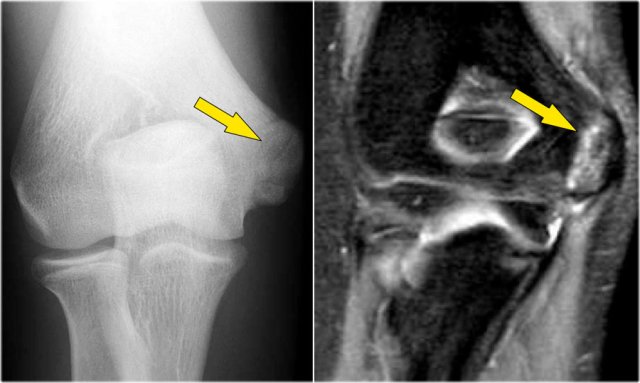

The radiograph is of a 15 year old baseball player with 4 year history of elbow pain and a recent episode of locking.

There is a focal lucency in the capitellum and some fragmntation.

This is typical for a osteochondral lesion of the capitellum and the locking is probably the result of loose bodies.

Continue with the MR...

The MR-arthrogram confirms the osteochondral lesion.

There is gadolinium in between the humerus and the osteochondral lesion which indicates that it is unstable.

If you don't have gadolinium, look for joint fluid undercutting the fragment.

There is a loose body in the posterior recess of the radiocapittelar joint.

Notice also the fragmentation as seen on the axial image.